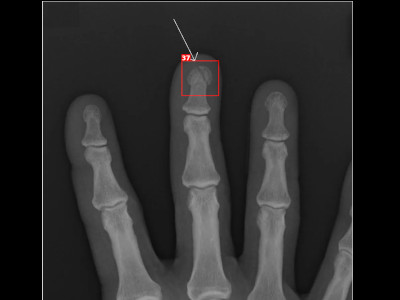

Detecção de fratura da falange distal em Raio X

Fratura da falange distal